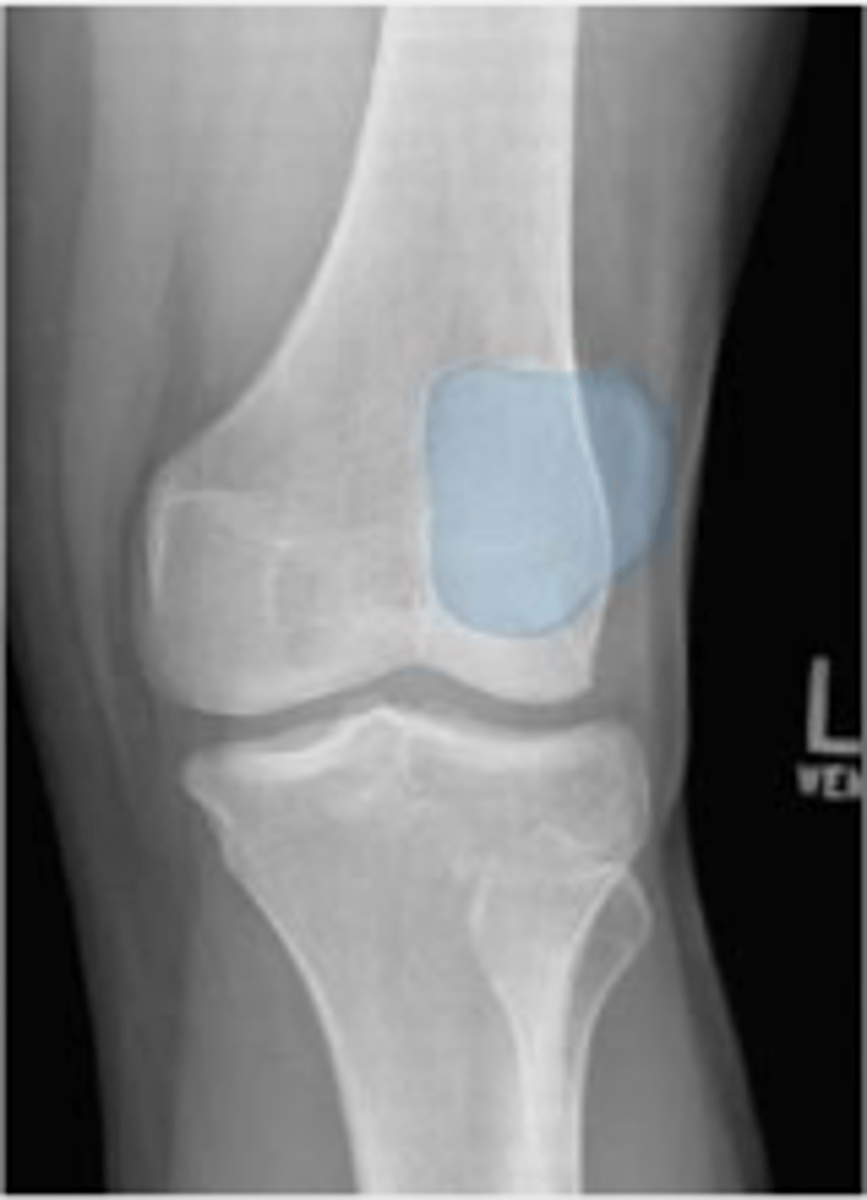

Patellofemoral joint space of the left knee

What joint space is the arrow pointing to?

Left patellofemoral joint space

What space are the arrows pointing to?

Left patella

What is outlined?